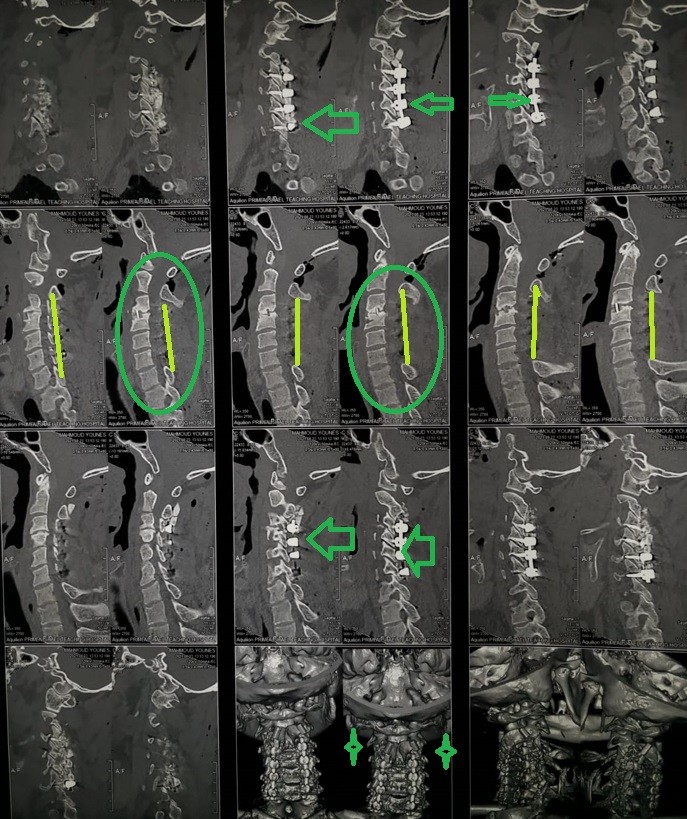

Fixation and dilatation of the cervical nerve canal to correct unsuccessful anterior cervical discectomy